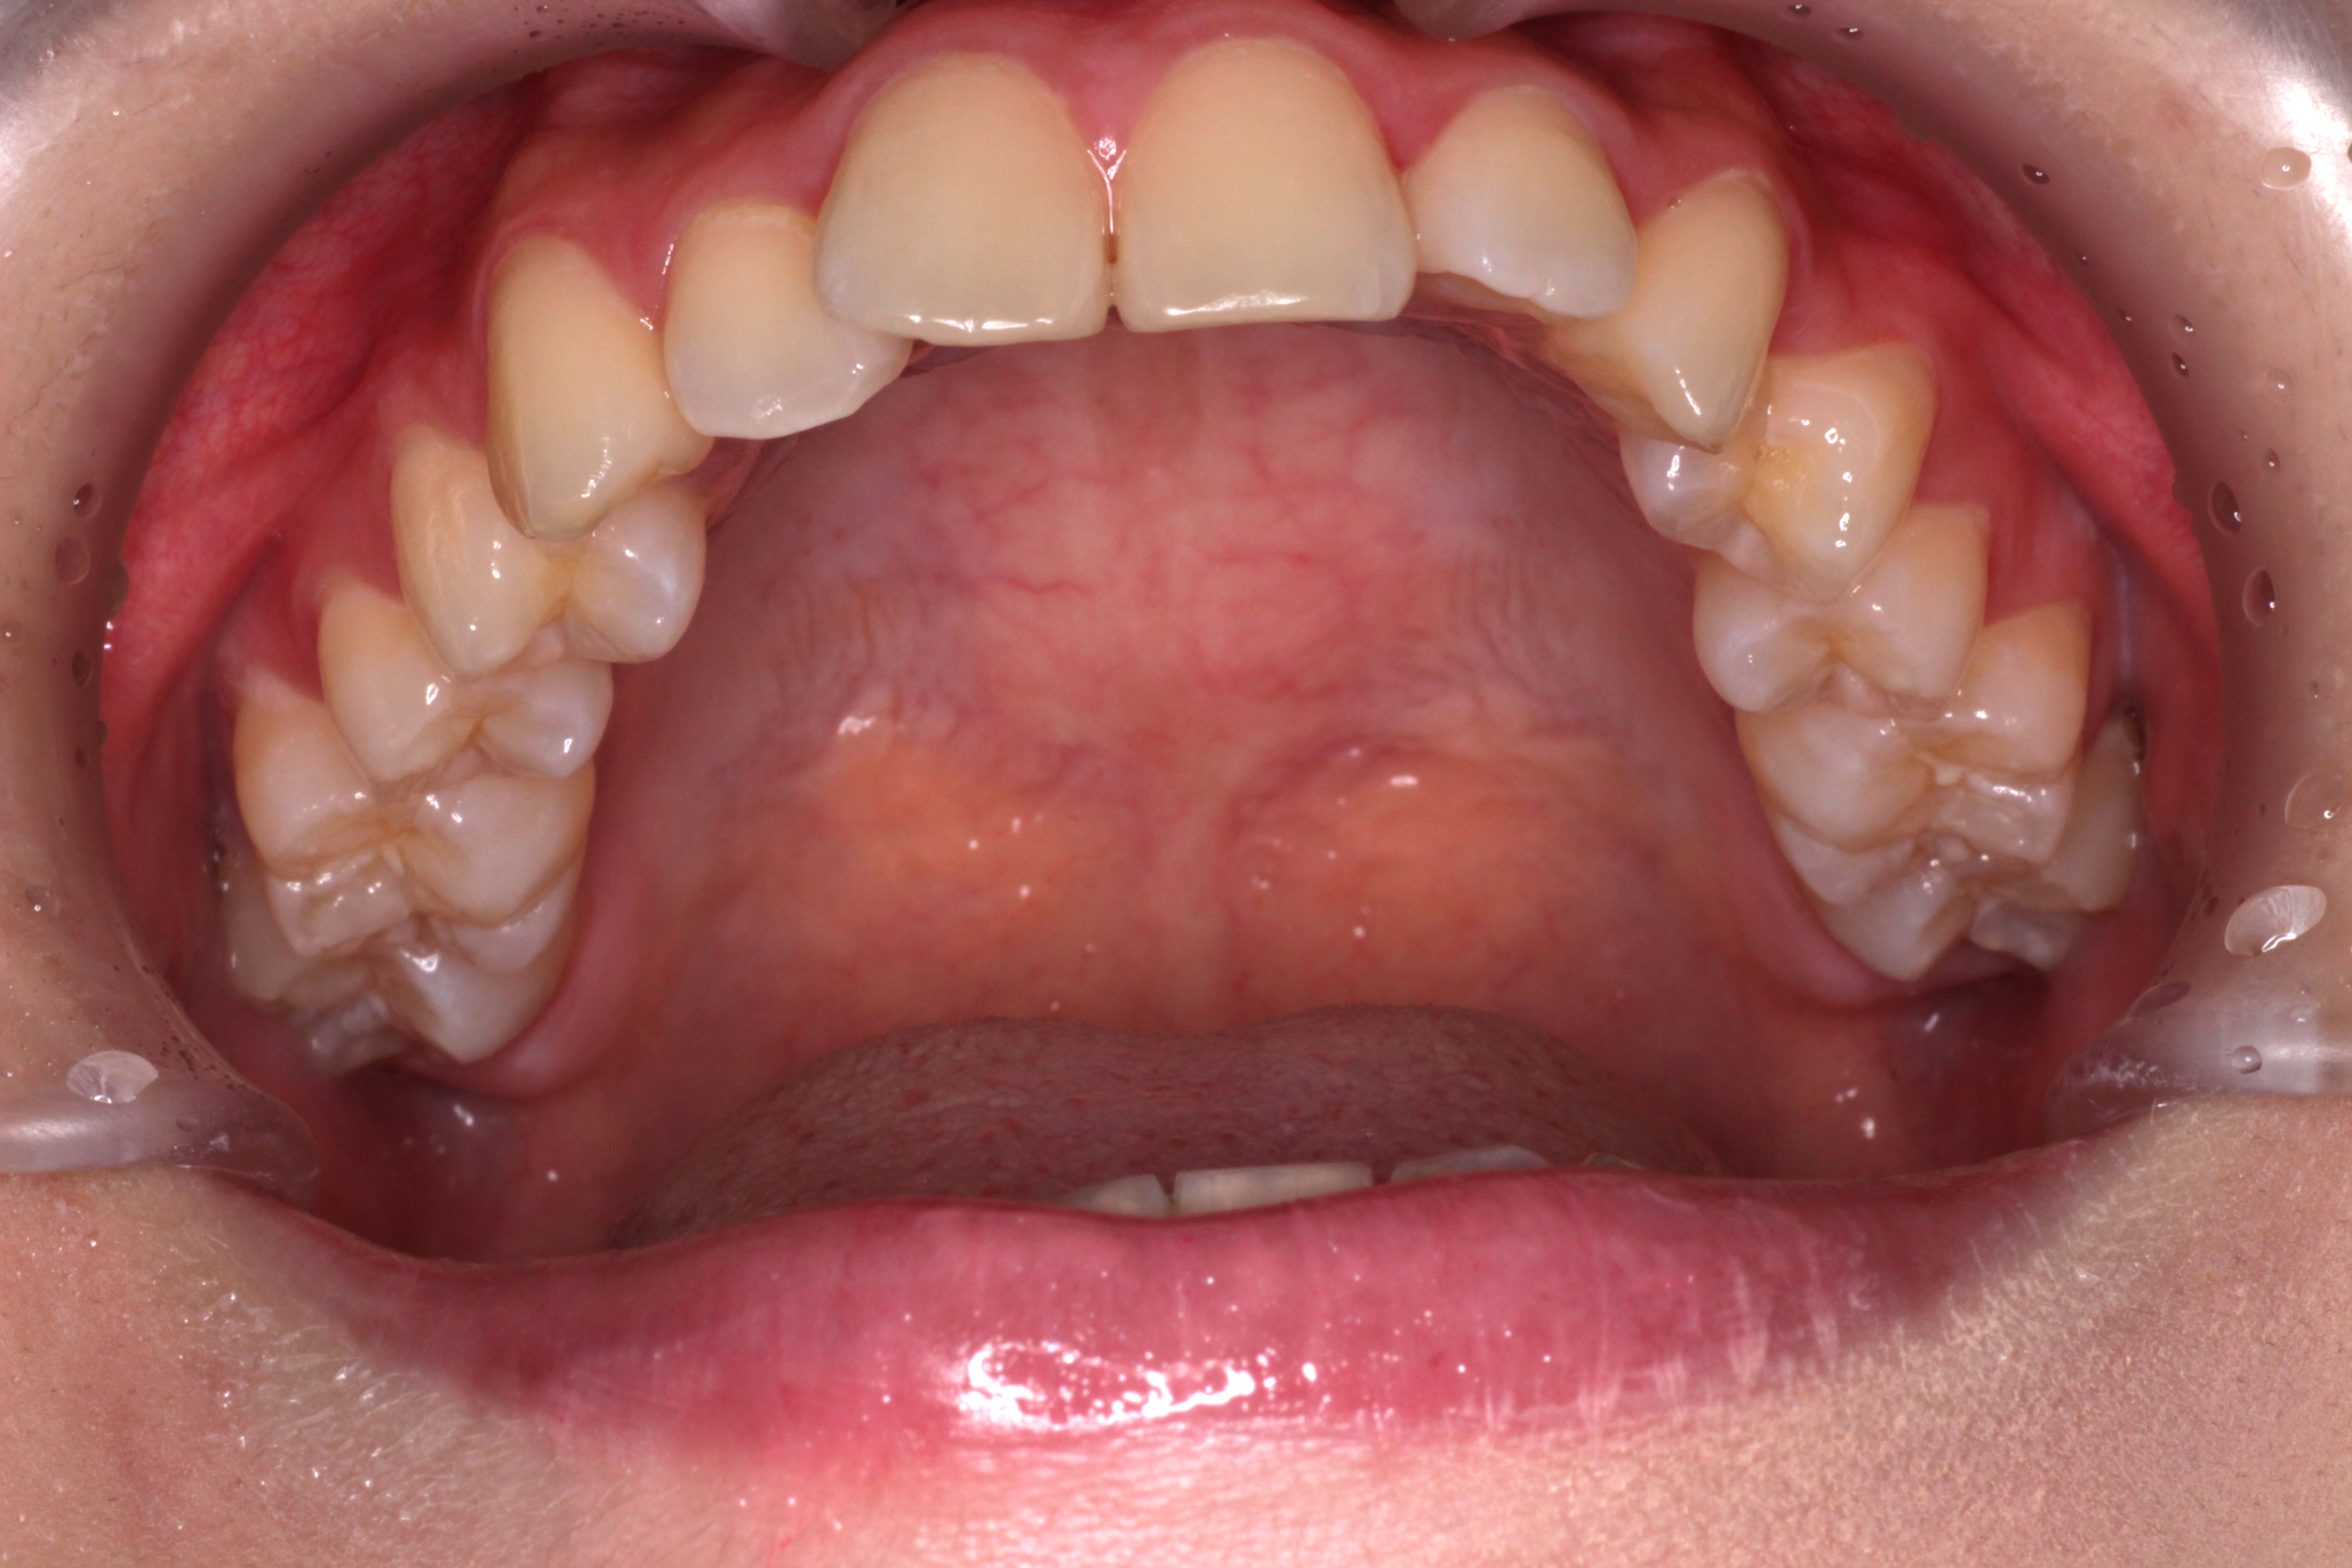

↓お口の中の状態です。

初診時からの変化と治すべきところは

⑴咬み合わせは下の歯が上の歯に隠れていましたが、見えるようになりました。

⑵右下の2番目の歯が歯列の中に納まってきましたが、まだ少しずれています。

⑶右上の2番目の歯は下の歯より前に出ましたが、咬み合わせが浅いです。

ここで新たな問題点が見つかりました。

⑷正中がずれているので、合わせるためにゴムかけをします。